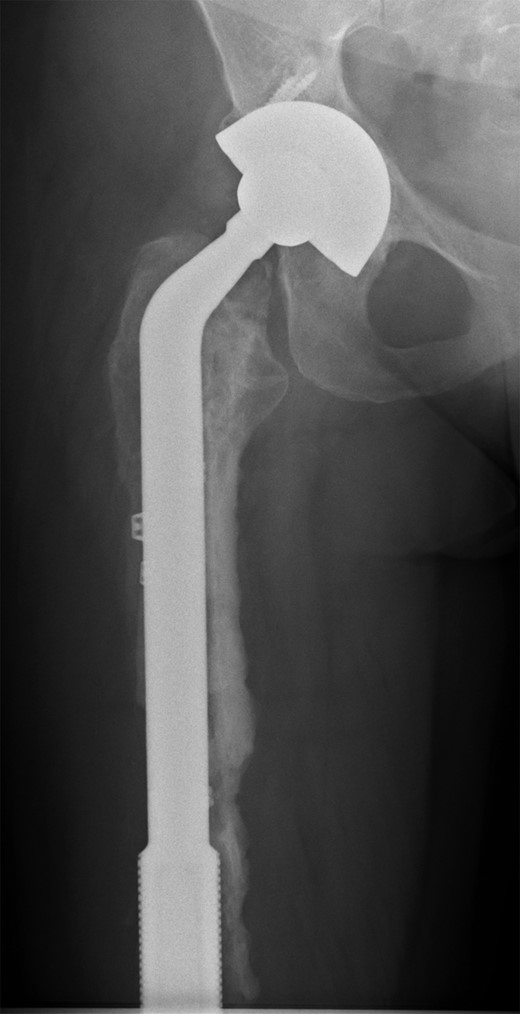

The operation was carried out by the senior author and the customized distal femoral prosthesis was successfully cemented over the pre-existing internal proximal femoral replacement (Figs 6 and 7).

Retained proximal femoral component with new custom-made cement-linked distal femoral prosthesis visible in lower half of the image.

New custom-made distal femoral prosthesis cement-linked to original salvage proximal femoral component visible in upper half of the image.